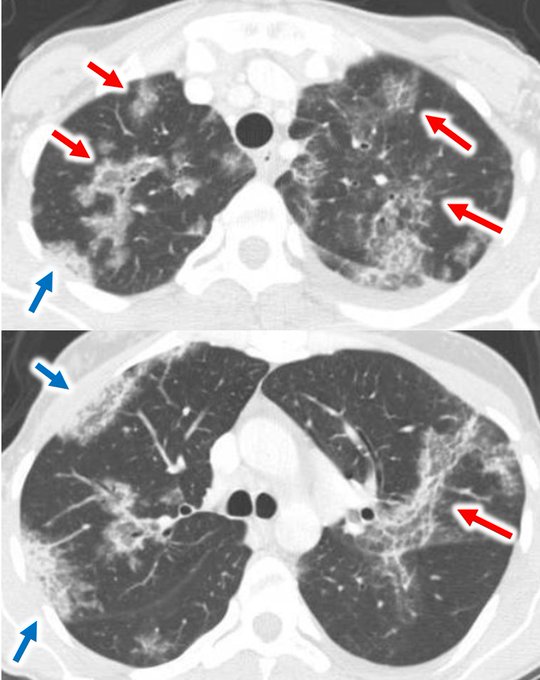

胸部CTでは、両側性のすりガラス影や浸潤影が主体で、その分布は非区域性・ランダムを基本としつつ、時に中枢優位、あるいは末梢優位となるなど多様性を示します。

(赤矢印:ランダム〜中枢優位のすりガラス影・浸潤影、青矢印:胸膜直下の非区域性浸潤影)